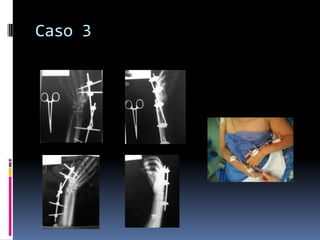

Caso 26 semanas después…Caso 3Femenino de 51 años

Ama de casa

Diestra

Caida de una sillaCaso 3

Caso 26 semanasdespués…Caso 3Femenino de 51 años

• 52.

• 53.

• 54.

Caida de unasillaCaso 3